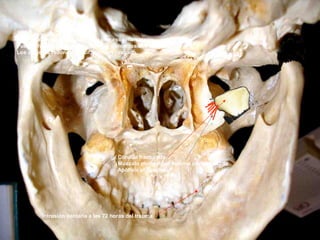

Cóndilo

Apófisis estiloides

Apófisis pterigoides

Vómer

Apófisis basilar

Foramen magnum

Intrusión dentaria a las 72 horas del trauma